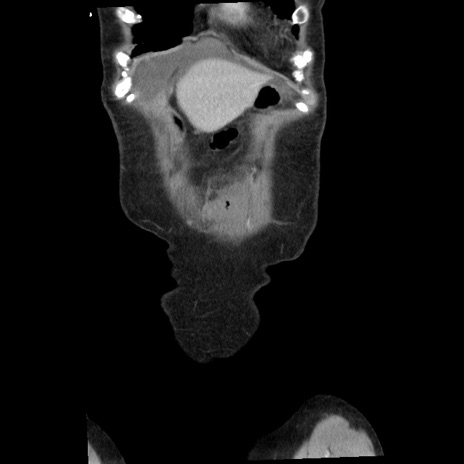

横断像